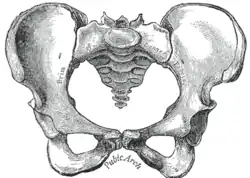

Pelvimetria

Pelvimetria é a medição da pelve feminina.[1] Teoricamente, pode identificar a desproporção céfalo-pélvica, que ocorre quando a capacidade da pelve é inadequada para permitir que o feto atravesse o canal de parto. No entanto, evidências clínicas indicam que todas as gestantes devem ter direito a um trabalho de parto de prova, independentemente dos resultados da pelvimetria.[2]

Os termos usados na pelvimetria são comuns em obstetrícia. A pelvimetria clínica tenta avaliar a pelve por exame clínico. A pelvimetria também pode ser realizada por radiografia e ressonância magnética.

A obstetrícia tradicional caracterizou quatro tipos de pelves:

- Ginecoide: forma ideal, com abertura superior arredondada a levemente oval (entrada obstétrica ligeiramente menos transversa).

- Androide: abertura triangular, espinhas isquiáticas proeminentes, arco púbico mais angulado.

- Antropoide: o maior diâmetro transverso é menor que o diâmetro obstétrico ântero-posterior.

- Platilipeloide: abertura superior achatada, com diâmetro obstétrico reduzido.